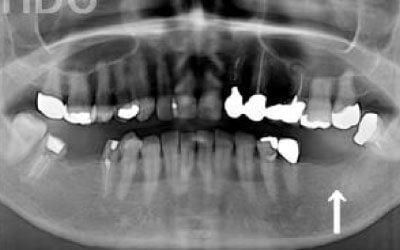

しばらくすると、抜けたままでも慣れてしまうことがありますが、その後に大きな問題が生じることがあります。

1 周囲の歯が早く抜ける

抜けた歯にかかるはずだった噛む力が、知らず知らずのうちに他の歯に負担をかけてしまいます。その結果、残っている歯が突然折れてしまい、抜歯が必要になることがよくあります。

2 歯が傾いてくる、落ちてくる

歯は互いに支え合い、バランスを保っています。そのため、歯が抜けると支えがなくなり、抜けた部分の両隣の歯が傾いたり、上の歯が下に移動してきたりすることがあります。